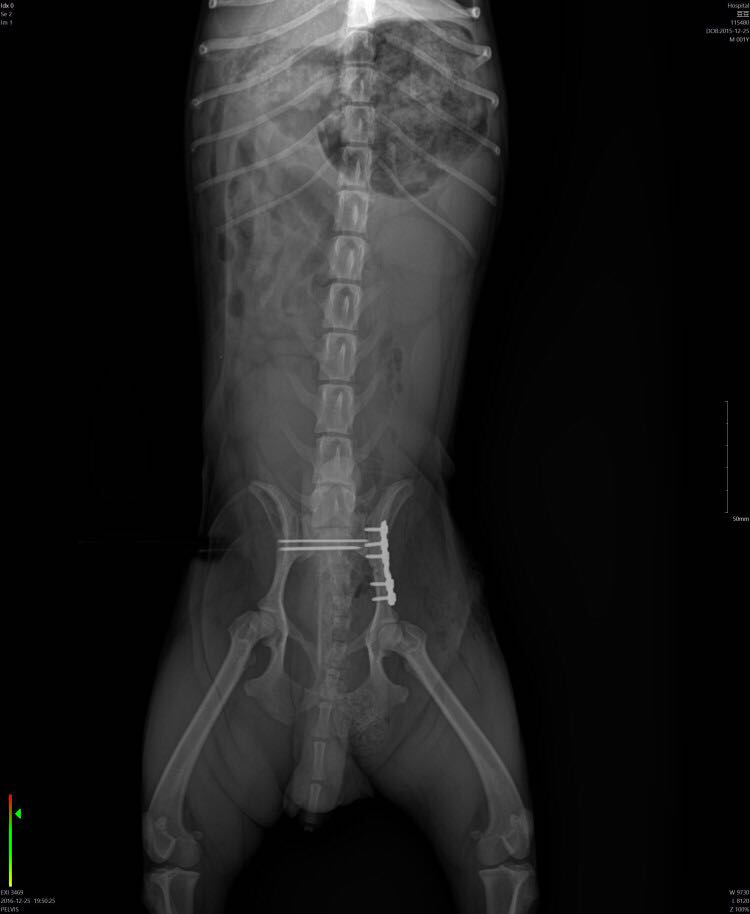

犬骨盆骨折内固定

犬骨盆骨折,多数情况是由于车祸导致,此图中的骨折犬就是 由于未拴犬链,被汽车撞伤,导致左侧髂骨体骨折,右侧见髂关节脱位,术后两个月恢复正常做了,所以动物主人遛狗时一定拴好犬链。